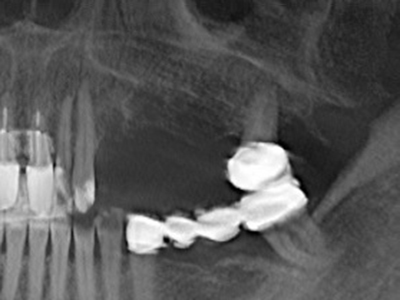

Indication: Sinus lift

Preparation of the lateral window during an external sinus floor elevation is challenging, particularly for implantologists with little surgical experience. Removal of the bone cover of the sinus without injuring the underlying Schneiderian membrane is only part of the operation – after establishing an adequate access, the membranous lining of the sinus must be carefully mobilized to make space for the augmentation materials or the implants. Piezosurgery is useful for this indication in two ways: diamond-coated instruments can be used for selective bone ablation and the underlying mucous membrane remains intact when the procedure is done carefully. The ultrasonic frequencies also enable detachment of the mucous membrane without complications – the frequencies are transmitted into the space between the mucous membrane and sinus floor by special blunt attachments (Cassetta, Ricci et al. 2012, Pereira, Gealh et al. 2014) (Rickert, Vissink et al. 2013). As a result, it is not surprising that current reviews of external sinus floor elevation positively evaluate the use of piezoelectric devices as well as the use of roughened implant surfaces and bone replacement materials (Wallace, Tarnow et al. 2012).